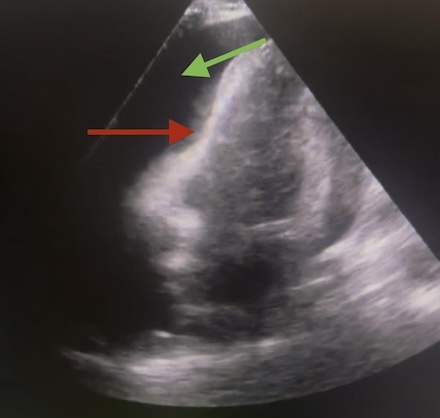

A 45-year-old male with hypertension presented with chest pain, cough, and malaise. Chest computerized tomography (CT) revealed right upper lobe pneumonia and several acute and chronic rib fractures. He was tachycardic, febrile (102.9°F), and hypoxic. Labs showed leukocytosis (19.8) and elevated lactate (2.5). Electrocardiogram demonstrated low voltage (Figure A). Bedside trans thoracic echocardiogram (TTE) showed large pericardial effusion with right ventricular collapse (Figure B). Thus, a drain was placed, releasing 850 mL of purulent fluid. Post drainage, formal TTE revealed small residual effusion (Figure C). Vancomycin, cefepime, and metronidazole were started. Fluid studies showed 32,000 cells (91% neutrophils). Fluid cultures grew streptococcus pneumoniae. By day seven, the drain produced less than 50 mL over the previous twenty four hours. Bedside echocardiogram was confirmatory, so the drain was removed. The patient was discharged on six weeks of cefuroxime and a three month course of colchicine.